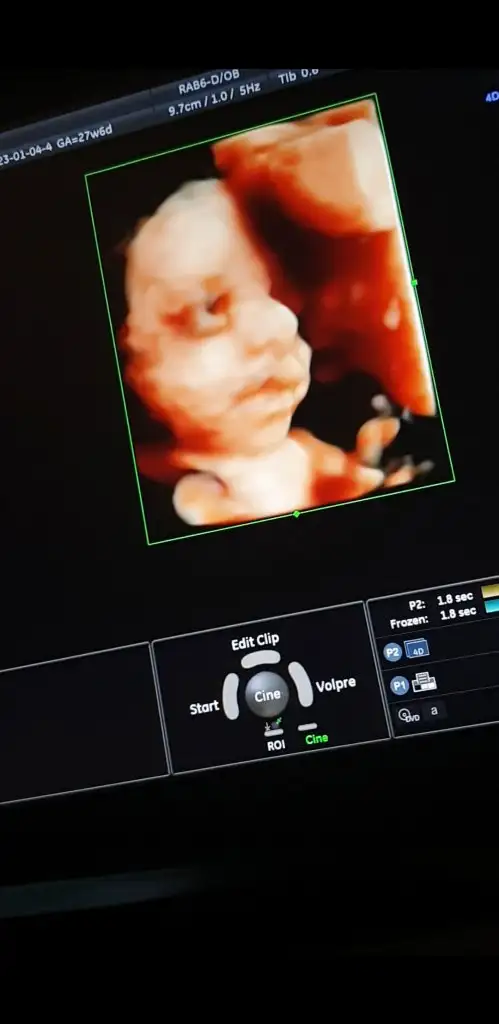

Kızlar iyi akşamlar, biraz önce kontrolden geldim, sat a göre 27+6 ama ultrasonda 27+4 çıktı, bebeğim 1120 gr - 36 cm olmuş🥰 rahim ağzı uzunluğum 4 cm üzeri çıktı.

Herşey yolunda gidiyor çok şükür, inşallah hiçbir problem çıkmadan hepimiz sağlıcakla doğururuz🙏

Video çekmiştim ondan kareler aldım😍

Her dururuşu bebeği değiştiriyor.

Screenshot_20230104-182322_Photos.jpg Screenshot_20230104-182558_Photos.jpg Screenshot_20230104-181937_Photos.jpg

Eki Görüntüle 3186715 Eki Görüntüle 3186714 Eki Görüntüle 3186716